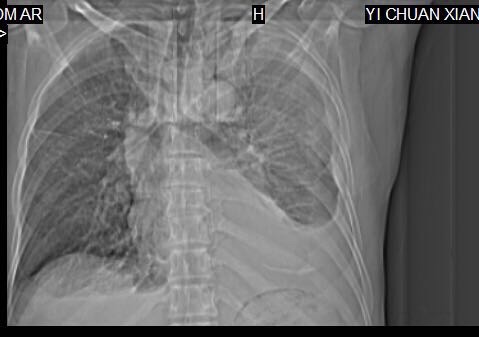

CT51232:胸腔积液 占位?

本帖最后由 cefcmj 于 2015-10-18 15:11 编辑 男性,自述感冒一周,用完感冒药后压气胸闷 咳嗽

左上肺可见斑片索条影,胸膜下见结节,左侧胸腔积液伴左下肺膨胀不全,考虑:左上肺结核,左侧胸腔积液。建议胸水常规检查。

左侧大量胸腔积液,建议胸水化验,是血性胸水还是结核性的,再进一步检查

左侧大量胸腔积液,有包裹,及叶间积液,不像肺癌,一般转移性积液不形成包裹

左侧大量胸腔积液,未见明确肿块影,建议抽胸水后复查CT。